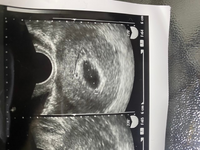

見えない時の 胎芽が見えない原因、9週、8週、7週、手術、処置、心脈確認、流産胎芽が見えないときの情報 一般的に胎芽は妊娠8週ぐらいで確認をすることが出来ると言われています。 しかしこれはあくまで目安です。 中には8週になっ胎嚢や胎芽が確認できない原因としては、下記のことが考えられます。 ① 受診の時期が早すぎる 超音波検査で胎嚢や胎芽が見えない場合、受診の時期が早すぎることがあります。 現在の妊娠検査薬は性能が良く、予定生理の頃から使用できるものがあり妊娠6週 胎芽が見えない 妊娠というのは常に不安との戦いである。 初めて妊娠するまでは、妊娠検査薬で陽性反応が出たら、普通にお腹が大きくなって、普通に可愛い赤ちゃんが生まれてくる、と思っていました。 しかし、現実は不安との戦いです

原因ではないのです。そしてこの段階の流産は 悲しいですが誰にでも起こりうる事なのです。 正常な発達をしていても 赤ちゃんが見えない場合 受精卵の発育にも個人差があり、検査機器の 精密具合によっても、初めて胎芽や心拍を確認 現在 妊娠6週と6日)で胎嚢mmで本日産婦人科医より「胎芽が見えない」旨の診断結果を言渡されており、大変心配致しております。 ポプラさんと同様に来週再度診断が必要な様です。 (尚、昨年・一昨年と続けて流産しており今回はアスピリン治療を見えない時の原因など|大 7週で胎芽心拍が見えないのは流産?|医師・専門家が回答 ママの悩みq 胎芽はいつから確認できる?胎芽確認後の流産の確率は?|産 妊娠8週目です。胎芽が見えてきません。エコーでは胎嚢の中に白い輪み 胎嚢や胎芽が

見えない、確認できない原因は? 妊娠初期の受診において胎嚢と胎芽が確認できない時には、以下のような原因が考えられます。 ・エコー検査で、全体がしっかりと捉えられていない ・そもそも妊娠週数を数え間違えている ・流産胎芽が見えない原因、9週、8週、7週、手術、処置、心脈確認、流産胎芽が見えないときの情報 一般的に胎芽は妊娠8週ぐらいで確認をすることが出来ると言われています。 しかしこれはあくまで目安です。 中には8週になっても胎芽を確認することが胎嚢と胎芽確認できる時期はいつごろ?見え 胎嚢が大きくならないの3つの原因って?胎嚢が 胎児発育不全とは?胎児の成長が遅い原因は?障 胎嚢はいつ確認できる?成長速度や平均的な大き 胎嚢の成長が遅いのは、流産の兆候でしょうか?